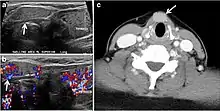

Fig. 4. A 45-year-old male patient presented with anterior mediastinal metastatic PTC lesions and occult primary on imaging. Histopathology examination of the resected thyroid gland revealed micro-foci of PTC; the largest, in the isthmus, measured 4 mm. a transverse greyscale ultrasound of the thyroid demonstrates homogeneous gland with normal echogenicity and size. No focal lesion or micro-calcifications. b Non-enhanced CT scan obtained as part of PET/CT examination shows a heterogeneous, large, relatively dense anterior mediastinal mass (white arrow) with peripheral calcification (arrowheads). Thyroid gland has normal CT appearance with no abnormal FDG uptake (not shown).[1]